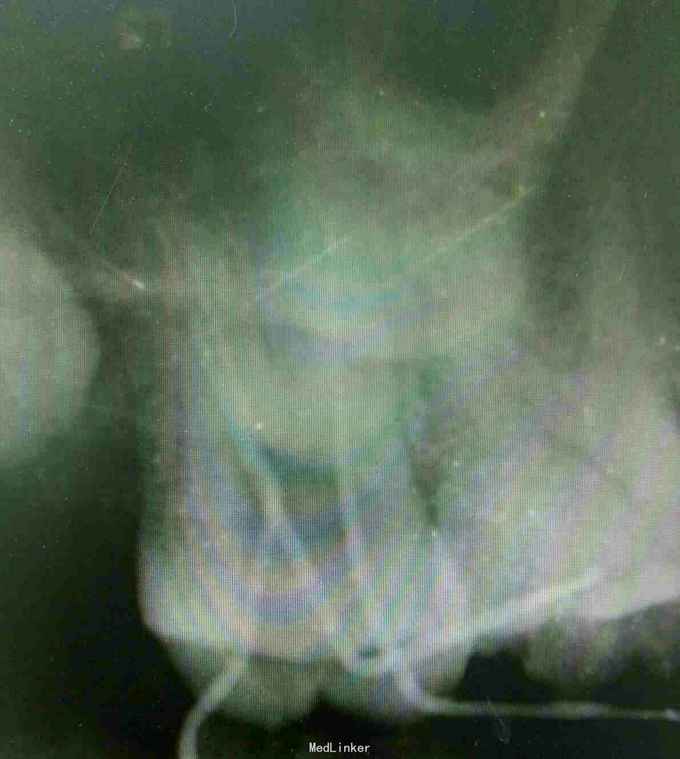

检查:17合面见牙色充填体,冷+,探-,叩不适,无松动,牙龈未见异常 x线:17冠方见高密度充填影像,近髓,近中根周膜略增宽 18低位阻生

诊断:17牙髓炎 治疗计划:17根管治疗术 处置:17开髓,揭顶,见少量渗出,探及MB、DB、P三个根管口,P疏通过程疼痛明显,干燥,置失活剂,氧化锌暂封 一周后复诊:主诉无不适,氧化锌暂封完整在位,去除氧化锌,清理髓腔,测量根管长度,MB=P=19mm,DB=21mm,根管锉扩大至MB、DB25#,P至35#,双氧水、生理盐水交替冲洗,干燥根管,髓腔置CP棉球,氧化锌暂封 一周后复诊:无不适,氧化锌暂封在位,去除暂封,试主尖,冷侧牙充填,根尖片显示:恰填。 一周后复诊:无不适,叩-,患者因经济原因拒绝修复治疗,去除暂封后,磷酸锌垫底,树脂充填,调合,磨光。